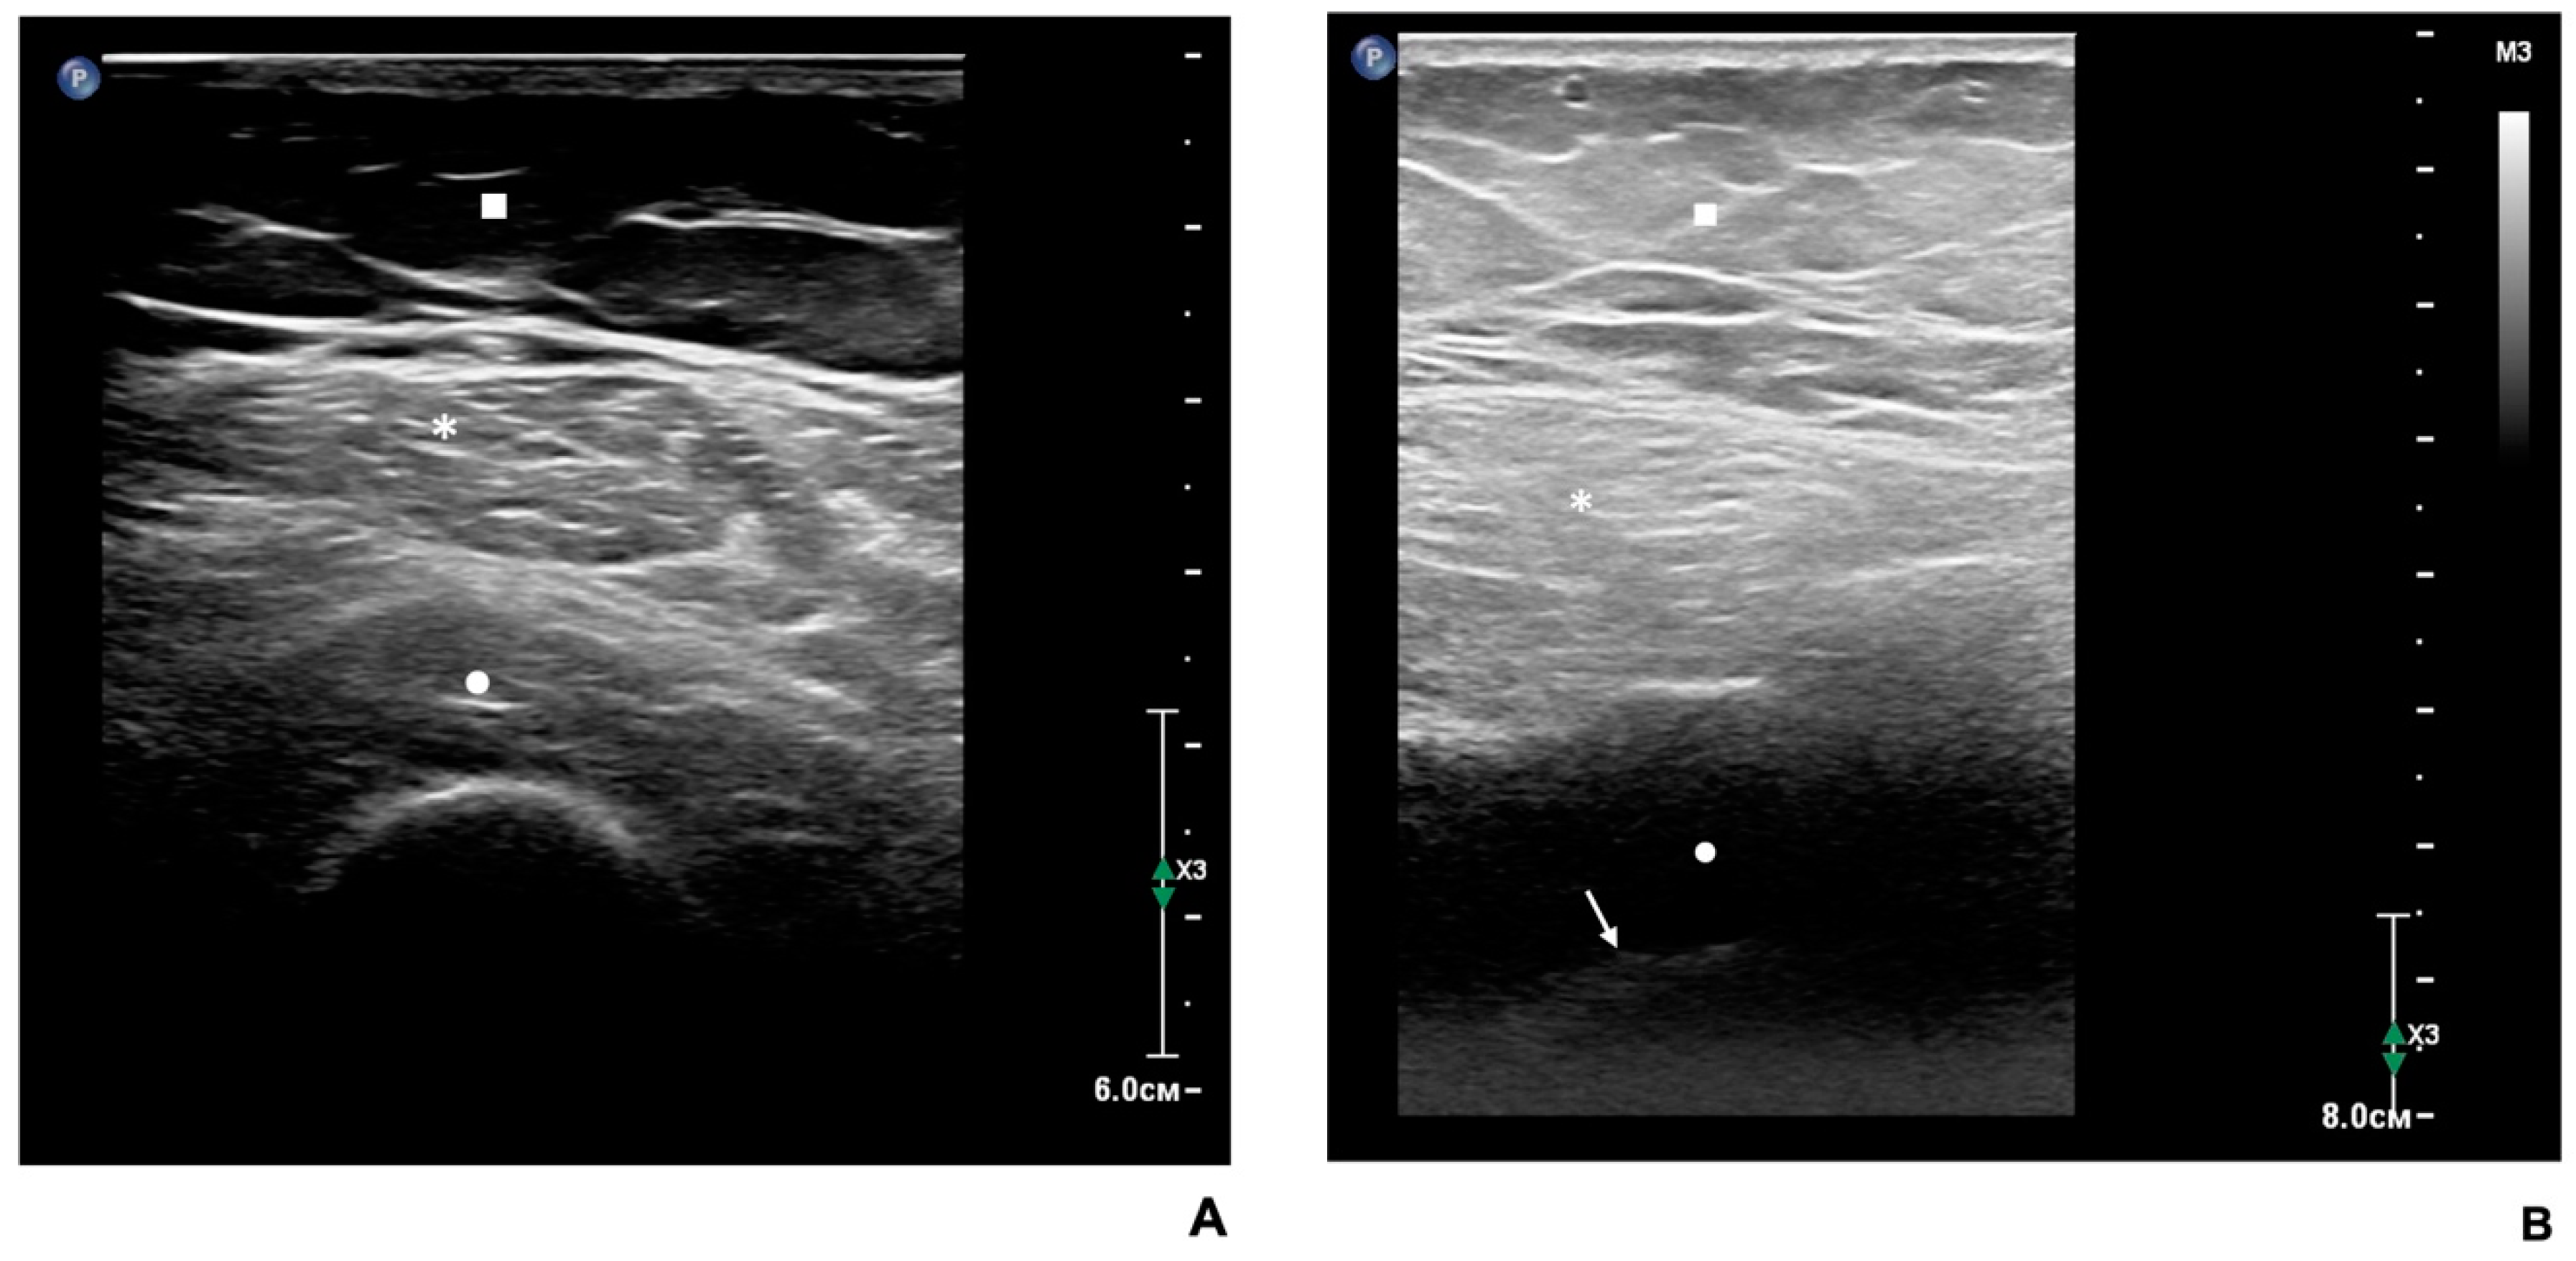

Table 5 summarizes the US imaging results of RFM in the dominant hip of study participants. Visual assessment of RFM by US in most patients corresponded to grade II according to the Hekmatt grading scale [19]. Similar numbers of patients (13 and 14) were classified as grade I or grades III–IV, respectively, on the Hekmatt grading scale. Patients with grades III and IV were pooled together due to the small number of patients with grade IV echo intensity. It should be noted that patients with grades III–IV RFM echo intensity had the highest BMI and BFP values vs. the patients with echogenicity grades I or II on the Heckmatt grading scale. However, patients with echogenicity grades I, II, or III-IV on the Hekmatt scale did not differ significantly from each other in age, gender, BMI, SMM, muscle strength, FLI values, presence of T2D, impaired fasting glucose levels, AH, and its stage. Ultrasound images of the RFM in patients with MASLD included in the present study are shown in Figure 2.

Figure 2. US images of the rectus femoris muscle (RFM) in patients with MASLD. (A) US image of the RFM of a female MASLD patient aged 68 years (body mass index = 24.7 kg/m2). RFM echo intensity suggests Heckmatt grade II, which implies increased muscle gray-scale level with still distinct bone echo. (B) US image of the RFM in a female MASLD patient aged 53 years (body mass index = 33 kg/m2). RFM echo intensity corresponds to Heckmatt grades III–IV, which suggests a marked increase in muscle gray-scale level with decreased bone echo (III) or complete loss of bone echo (IV). Square: subcutaneous fat; asterisks: RFM; circle: vastus intermedius. The arrow indicates the bone echo in (B).